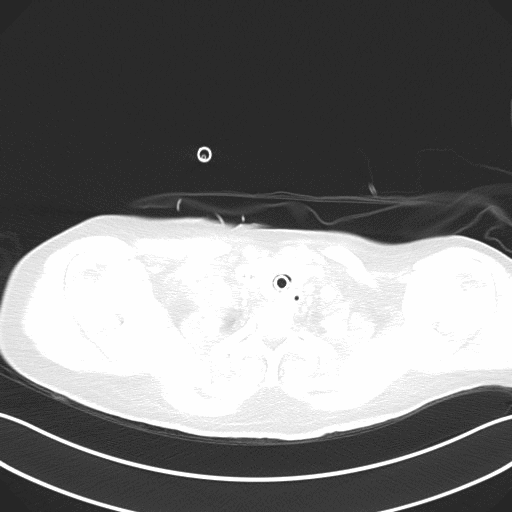

双肺散在小斑片状密度增高影、以双肺野中部显著

图1 患者入院时胸部X片(2021-06-12)

肺野具有特征性改变,双肺纹理明显增粗并模糊、双肺透亮度减低,

肺门影增大模糊不清,有散在粟粒状、小斑点状阴影出现,

以内中带为主,有发展至外带并呈中下肺野广泛分布